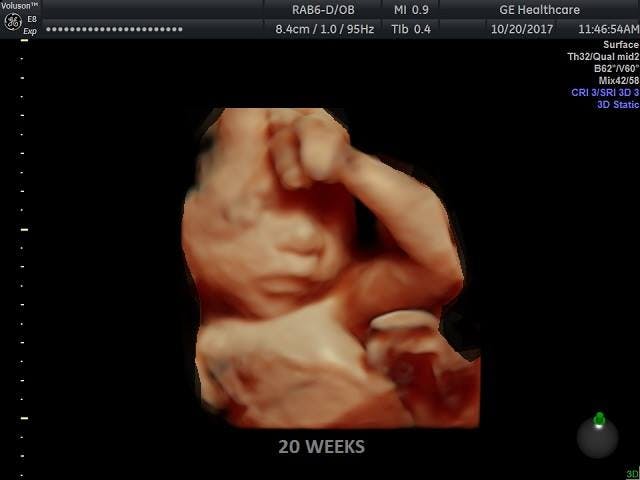

H.R. 36 was introduced based on modern science that has found that unborn babies are capable of feeling pain at least by twenty weeks’ gestation. And while viability is typically around 24 weeks, it is not unheard of for a baby much younger than that to survive – Frieda Mangold was born at 21 weeks in Germany and was able to go home with her parents. There will be more cases like hers as medicine continues to advance, and already, she is not the only baby to survive being born at 21 weeks.